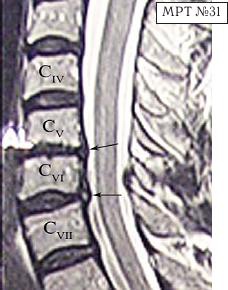

МРТ № 31

— мануальную терапию, с целью уменьшения (устранения) болевого синдрома, путём восстановления соотношений суставных поверхностей дугоотростчатых суставов в сегментах CV-CVI и CVI-CVII (устранение сублюксации);

— абсолютный стеноз спинномозгового канала шейного отдела позвоночника с полным блоком ликворных путей и сдавлением дурального мешка спинного мозга на уровне сегментов CV-CVI и CVI-CVII;

— в сегменте CV-CVI — значительный спондилёз, гипертрофия задней продольной связки, и практически компенсированная спондилёзом грыжа межпозвонкового диска;

— в сегменте CVI-CVII — довольно активная грыжа межпозвонкового диска;

— на уровне поражённых сегментов выраженный эпидурит.